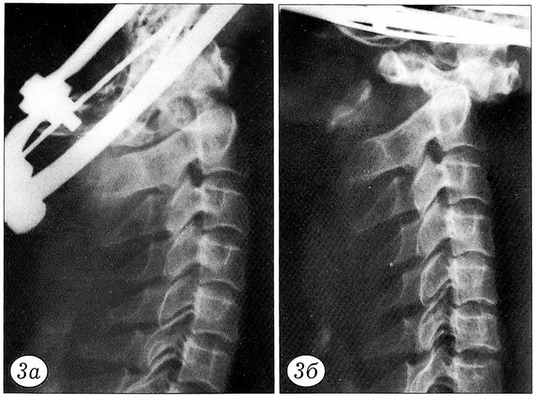

Результаты нагрузочного теста документировались графически. По оси ординат регистрировалось усилие в ньютонах, по оси абцисс — степень смещения позвонков в миллиметрах (рис. 2). При этом основное внимание уделялось величине нагрузки, при которой происходило наибольшее смещение позвонков. До и после нагрузочного теста производилась рентгенография блоков (рис. 3~5).

Рис. 3. Перелом зубовидного отростка С2 позвонка типа 2 до (а) и после (б) нагрузочного теста.